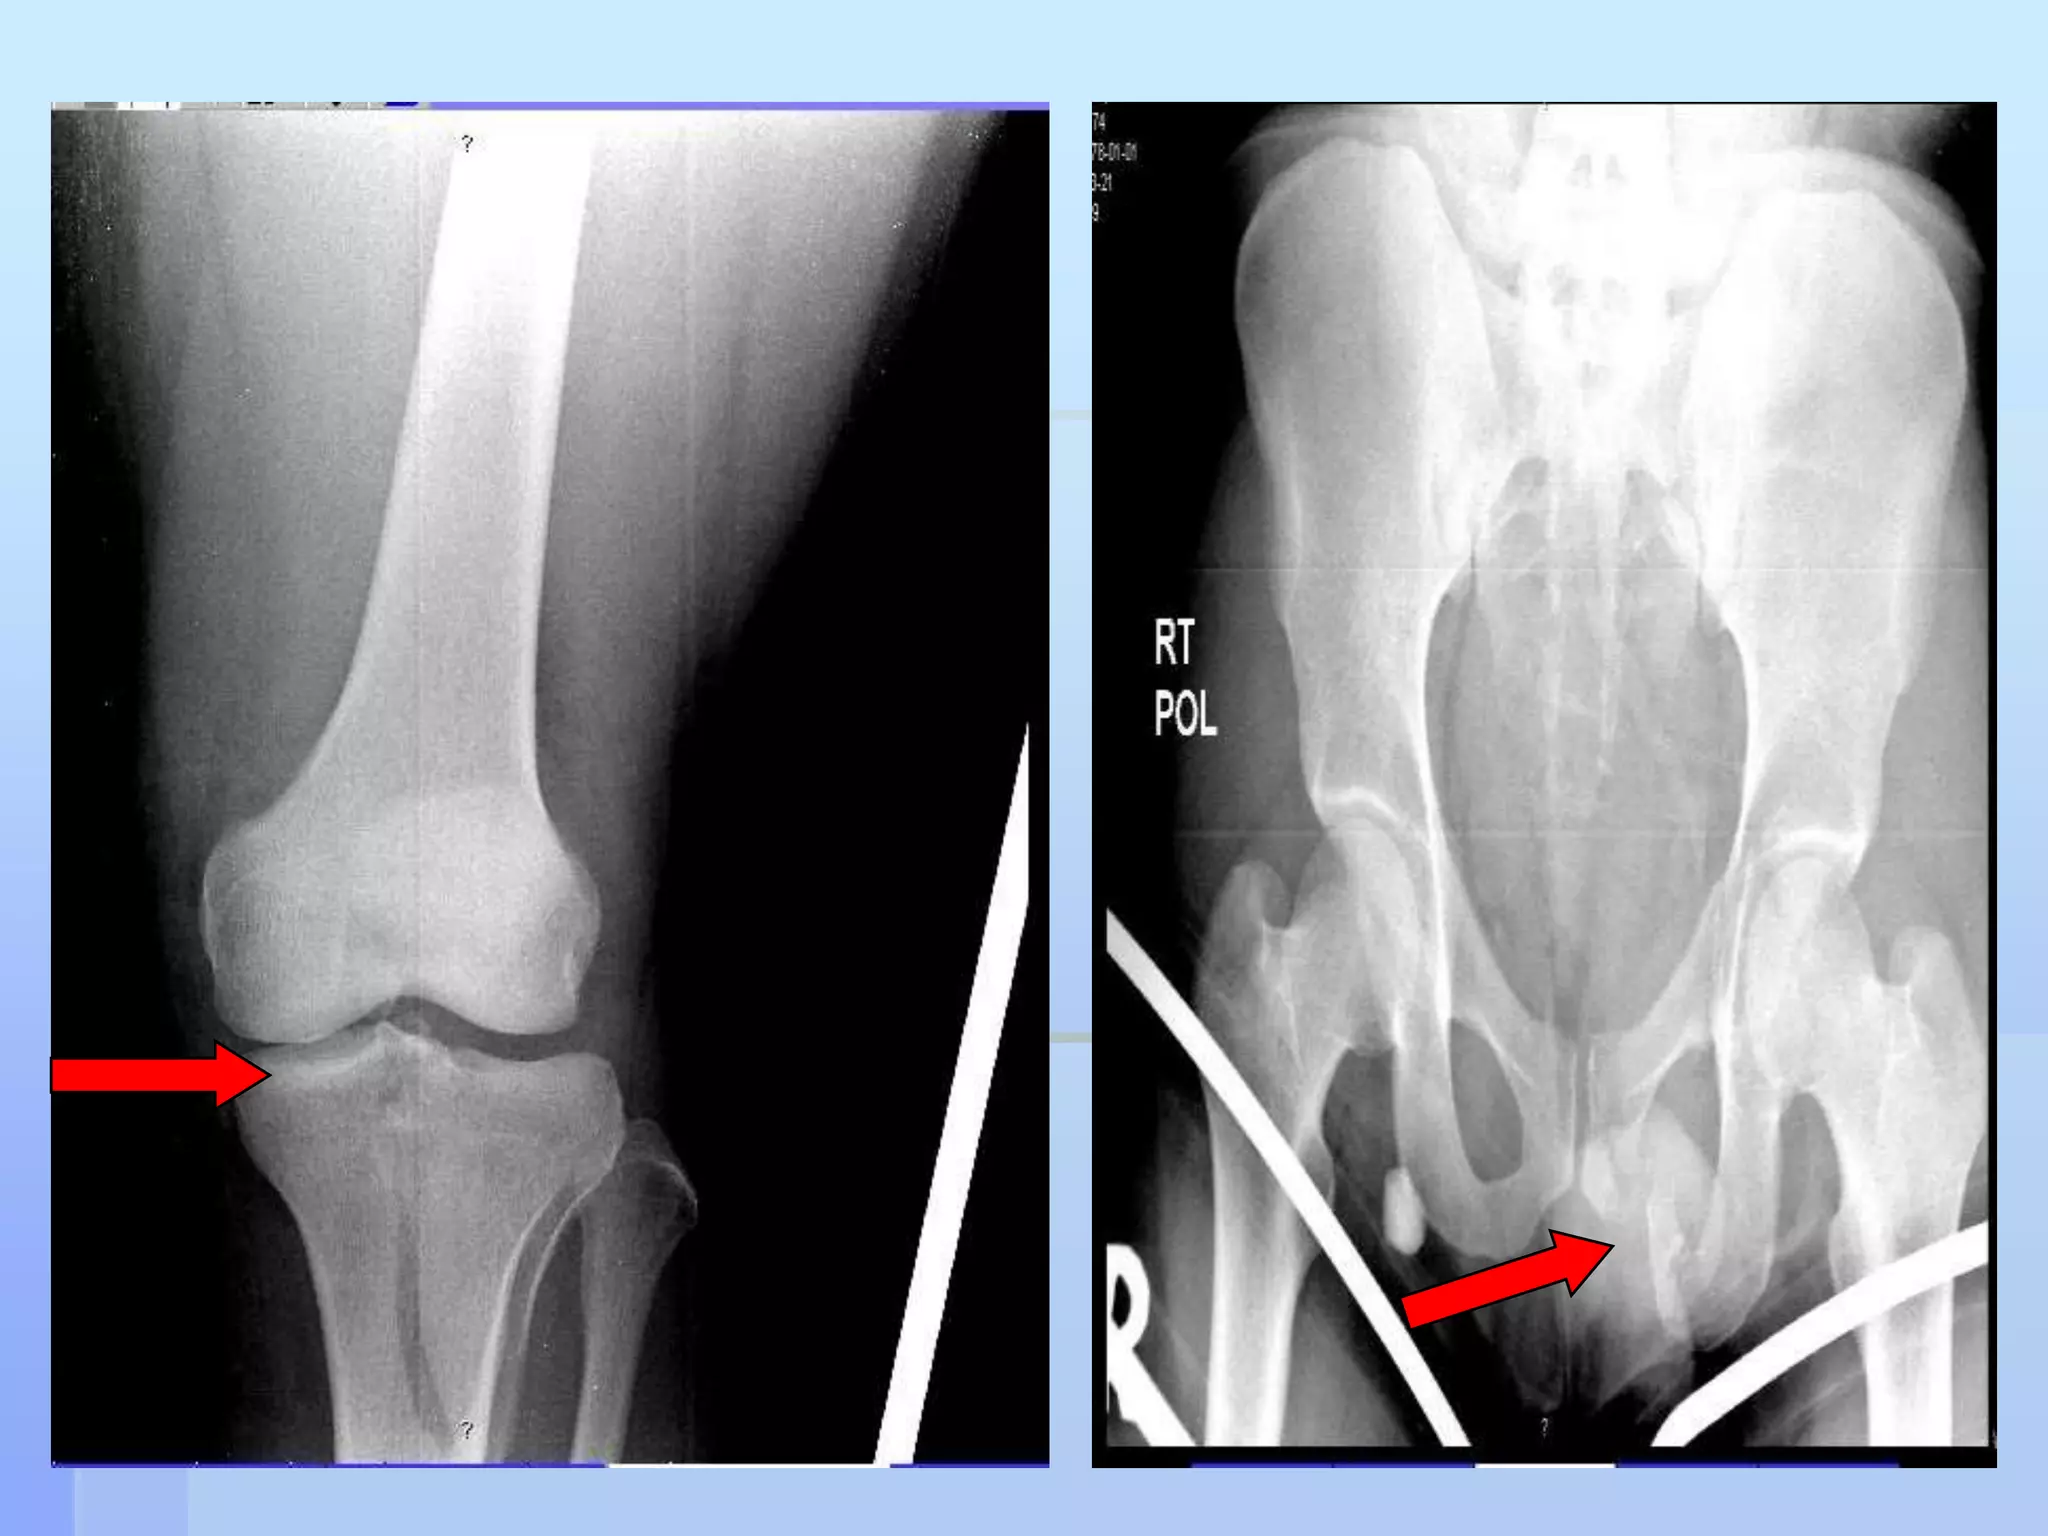

CASE 226 yrs Saudi, MaleRTA, intoxicatedBrought to ER Conscious, drowsy VS stable Bilateral knee pain & bruises Fracture Lt inferior ramus (pelvis)L.L. x-rays showed Rt tibial plateau fracture

CT angiogram was doneIt showed Vascular injury @ the level of             segment 2 of the Popliteal arteryNo distal run off

CASE 226 yrsSaudi, MaleRTA, intoxicatedBrought to ER Conscious, drowsy VS stable Bilateral knee pain & bruises Fracture Lt inferior ramus (pelvis)L.L. x-rays showed Rt tibial plateau fracture

CT angiogram wasdoneIt showed Vascular injury @ the level of segment 2 of the Popliteal arteryNo distal run off